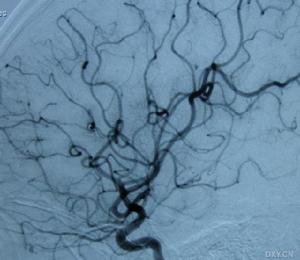

外傷後頸內動脈閉塞正常頸動脈前後位

1、腦血管造影可見患側頸內動脈顱外段阻塞,大腦中與大腦前動脈影像消失。